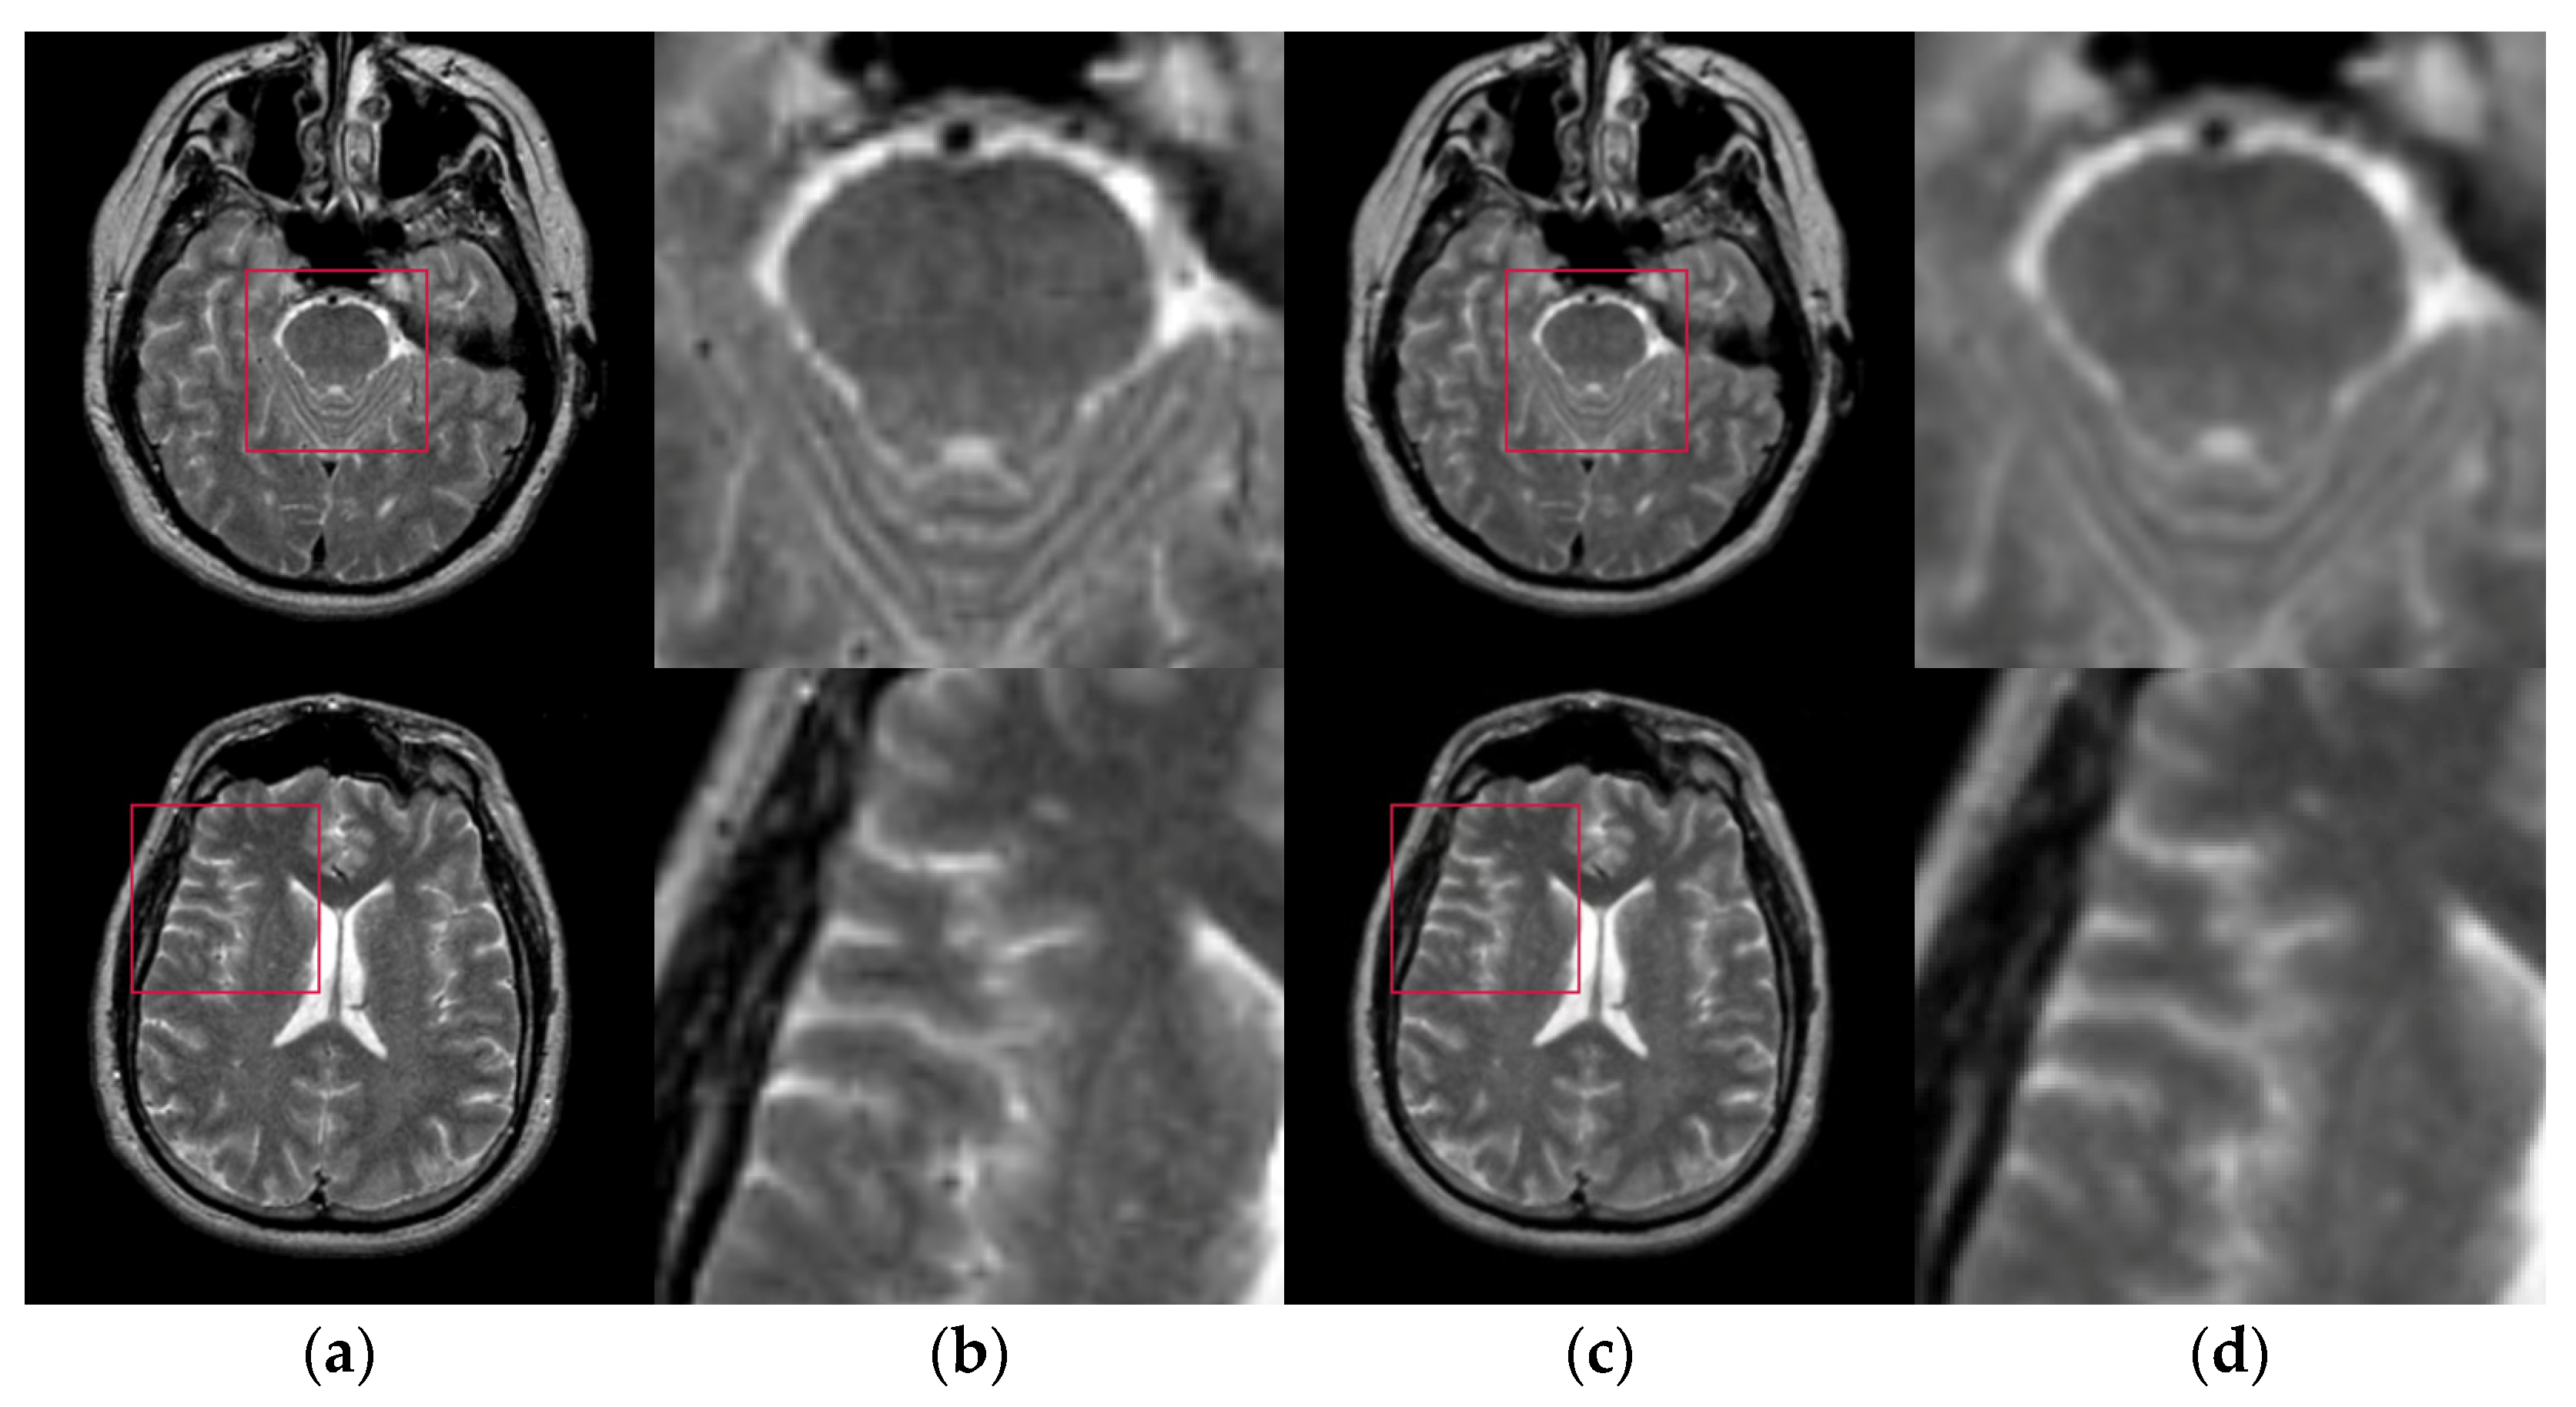

The test images we used in the experiments are from “The Whole Brain Atlas” of Harvard Medical School Image Library (http://www.med.harvard.edu/aanlib/home.html (accessed on 20 September 2021)). Due to limited space, we chose ten brain slices #022~#112 to demonstrate the performance of our proposed algorithm. These ten brain slices are shown in Figure 7. All the experiments in this paper are run on Intel(R) Core (TM) i7-7700HQ CPU @ 2.80 GHz 2.80 GHz, 16 GB RAM, windows 10 and programming language is Python3.6. The parameter settings of the proposed algorithm and the number of thresholds are shown in Table 1.

Figure 7.

Ten brain slices (a) slice #022, (b) slice #032, (c) slice #042, (d) slice #052, (e) slice #062, (f) slice #072, (g) slice #082, (h) slice #092, (i) slice #102, (j) slice #112.